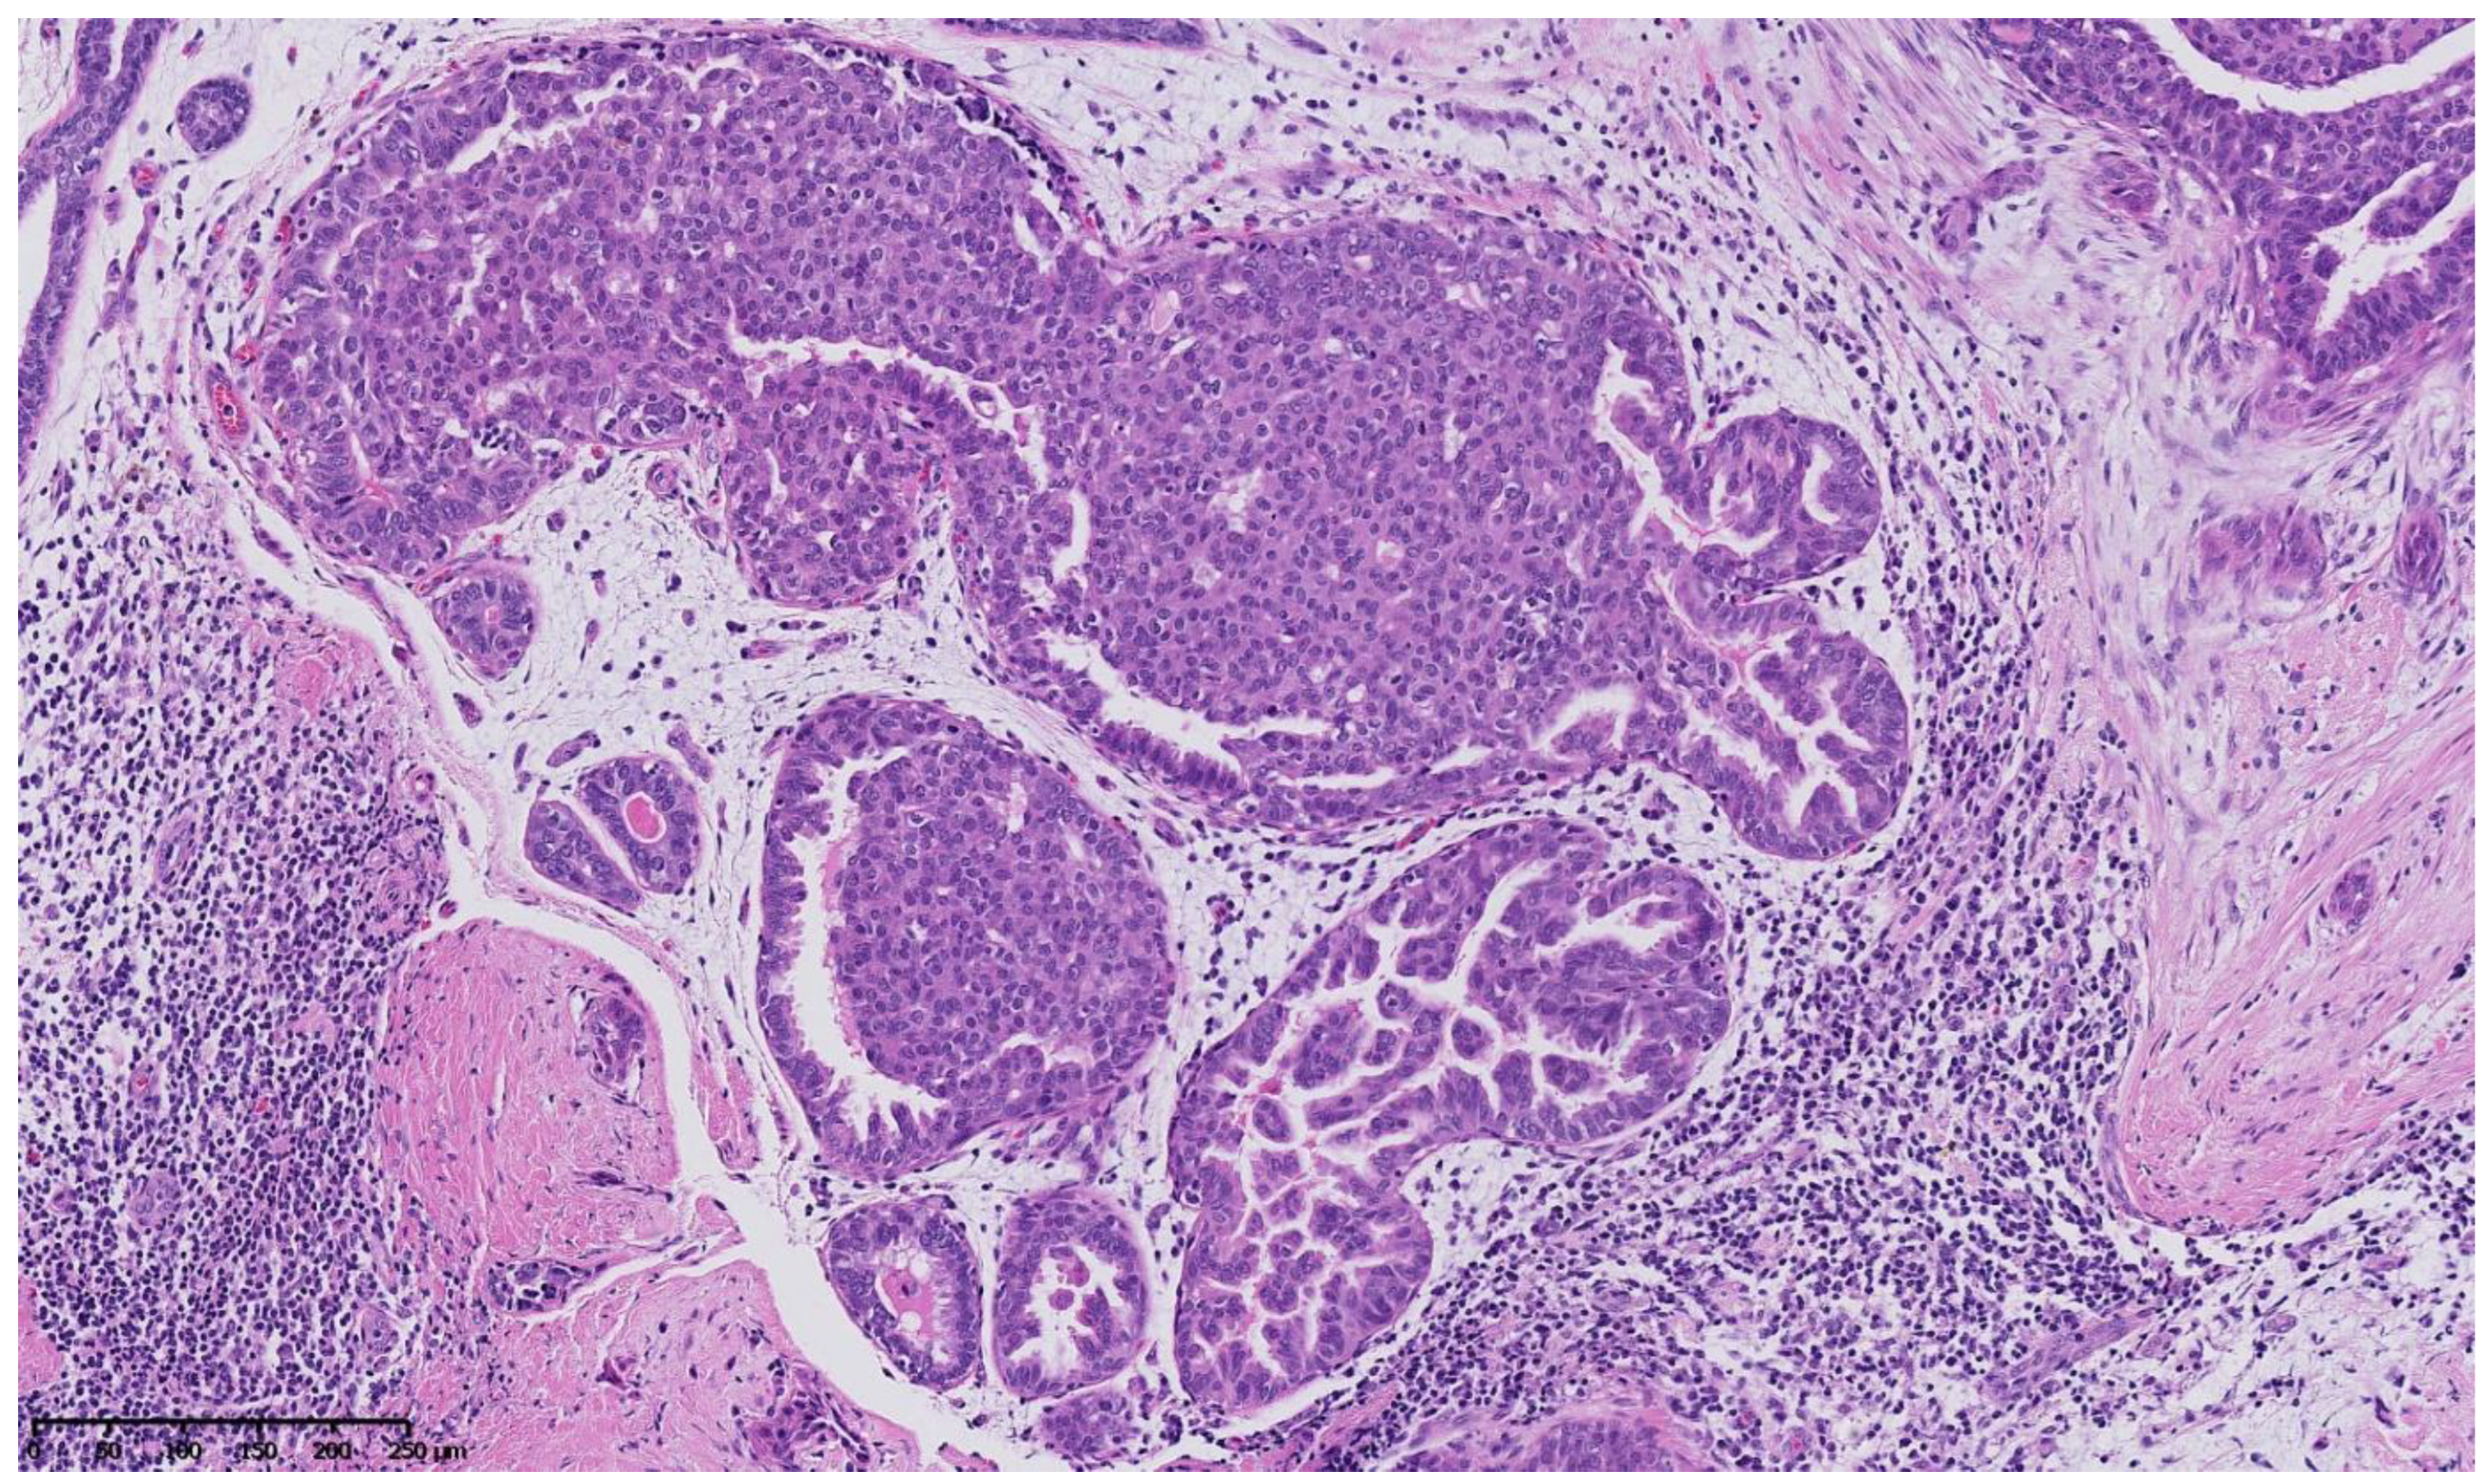

Figure 2, Figure 3, Figure 4, Figure 5, Figure 6 and Figure 7 describe a panel of different lesions observed in a patient treated for 2 years by natural estrogens and antiandrogens.

Figure 5.

Hematoxylin and eosin staining: at higher magnification, some intraepithelial proliferations are formed by stubby micropapillae with a heterogeneous nuclear population showing no significant cellular atypia, and some are of cribriform architecture with slit-like fenestrations and nuclear streaming, showing no significant cellular atypia either.